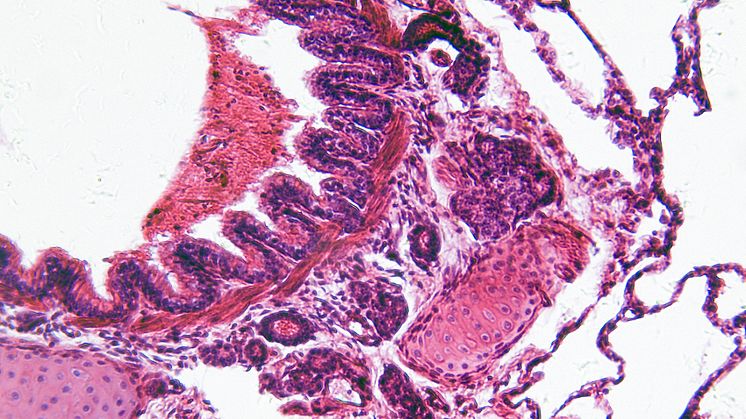

KOL, kronisk obstruktiv lungsjukdom, orsakas av små partiklar främst från cigarettrök som skapar en inflammation i lungvävnaden. Inflammationen läker inte ut utan fortsätter successivt att bryta ned vävnaden med allt svårare symtom som hosta, slembildning och andnöd. Det finns inga läkemedel som botar sjukdomen.

Mikroskopibilden ovan visar ett snitt från normal lungvävnad (istockphoto).